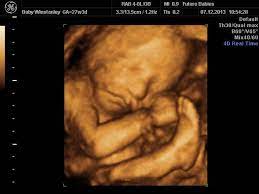

When Is It The Best Time To Do A 3d 4d Ultrasound December 2018 Babies Forums What To Expect

When Is It The Best Time To Do A 3d 4d Ultrasound December 2018 Babies Forums What To Expect from images.agoramedia.com